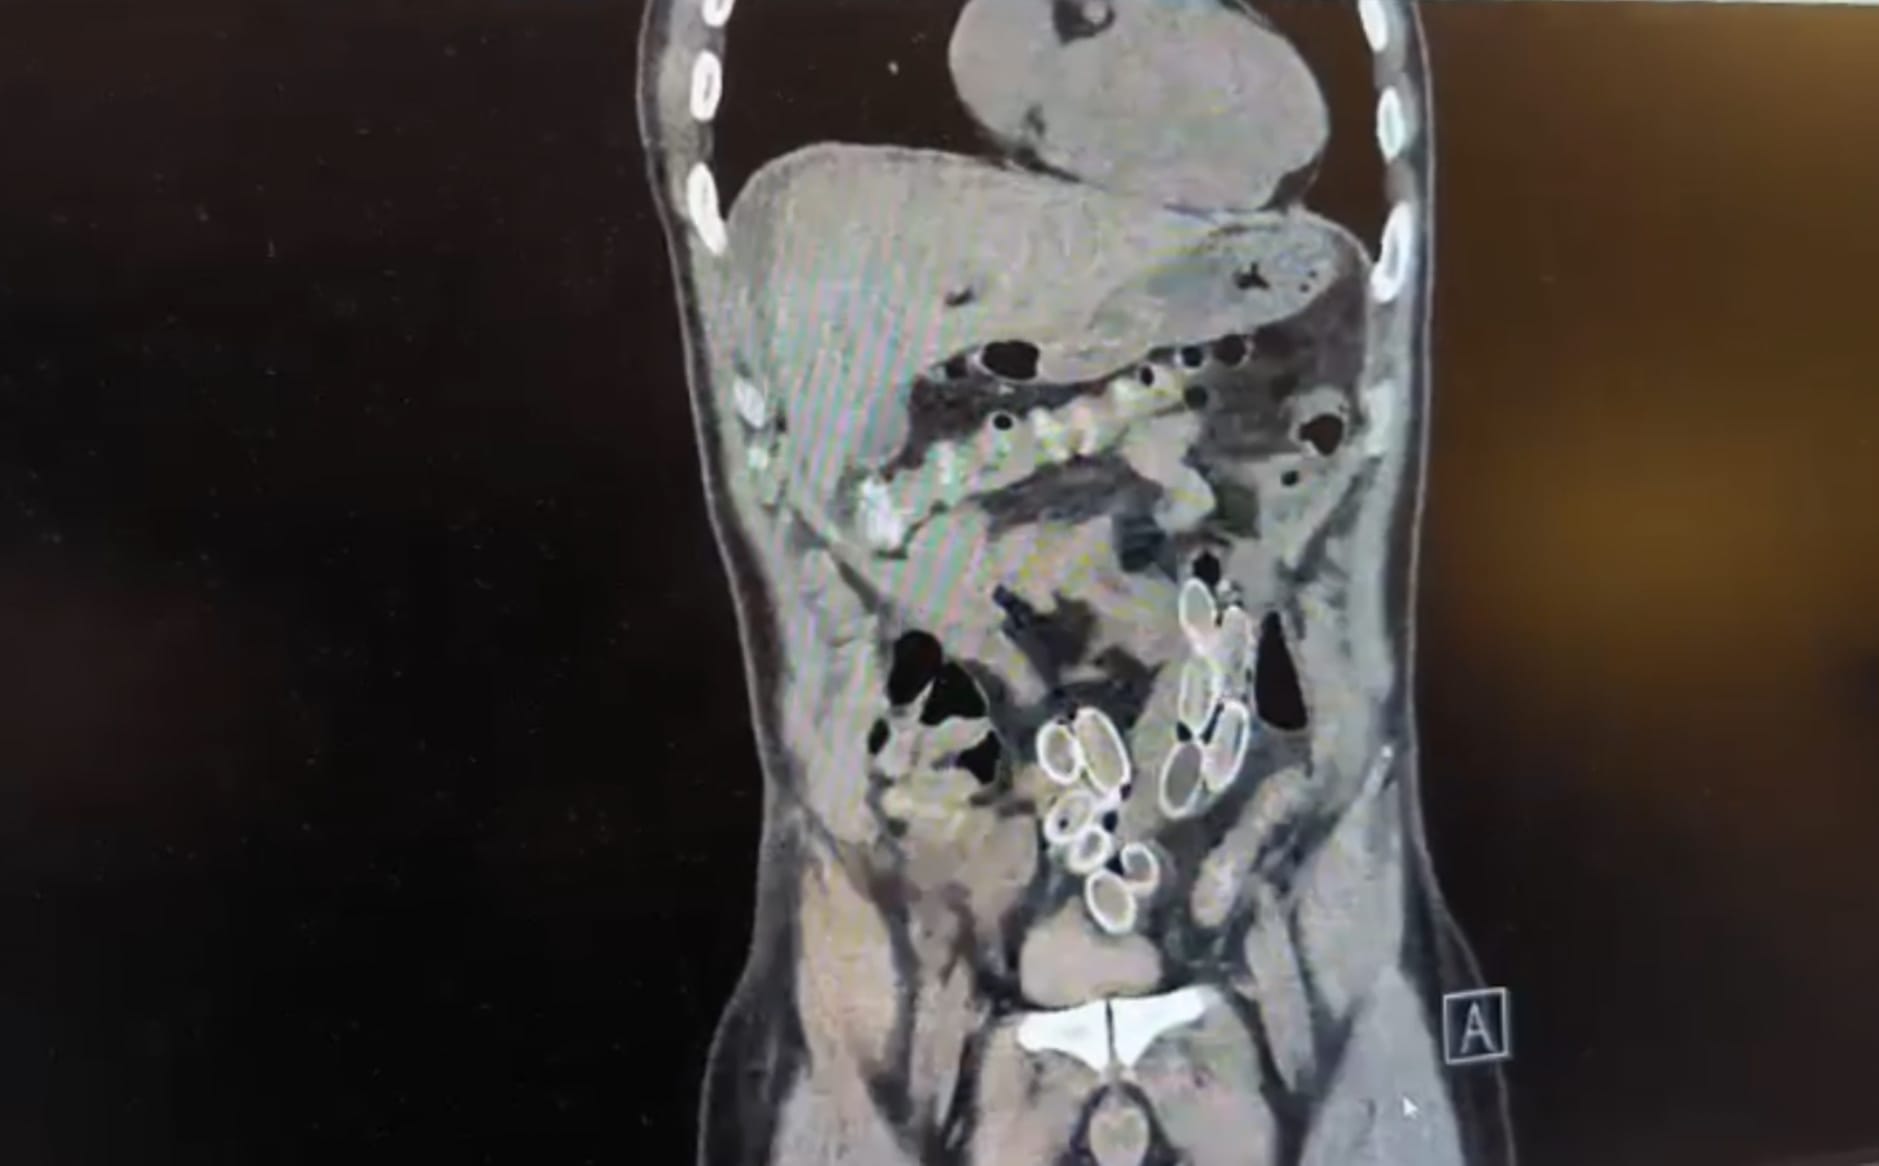

İhbar üzerine olaya ilişkin çalışma başlatan polis ekipleri, doktorlarla görüşme gerçekleştirdi. Ameliyata alınan şahsın mide ve bağırsaklarından, toplam ağırlığı 259,7 gram olduğu öğrenilen 49 esrar macunu çıkarıldı. Şüpheliye ait 1 adet cep telefonu da hastane yetkilileri tarafından polis ekiplerine teslim edildi.